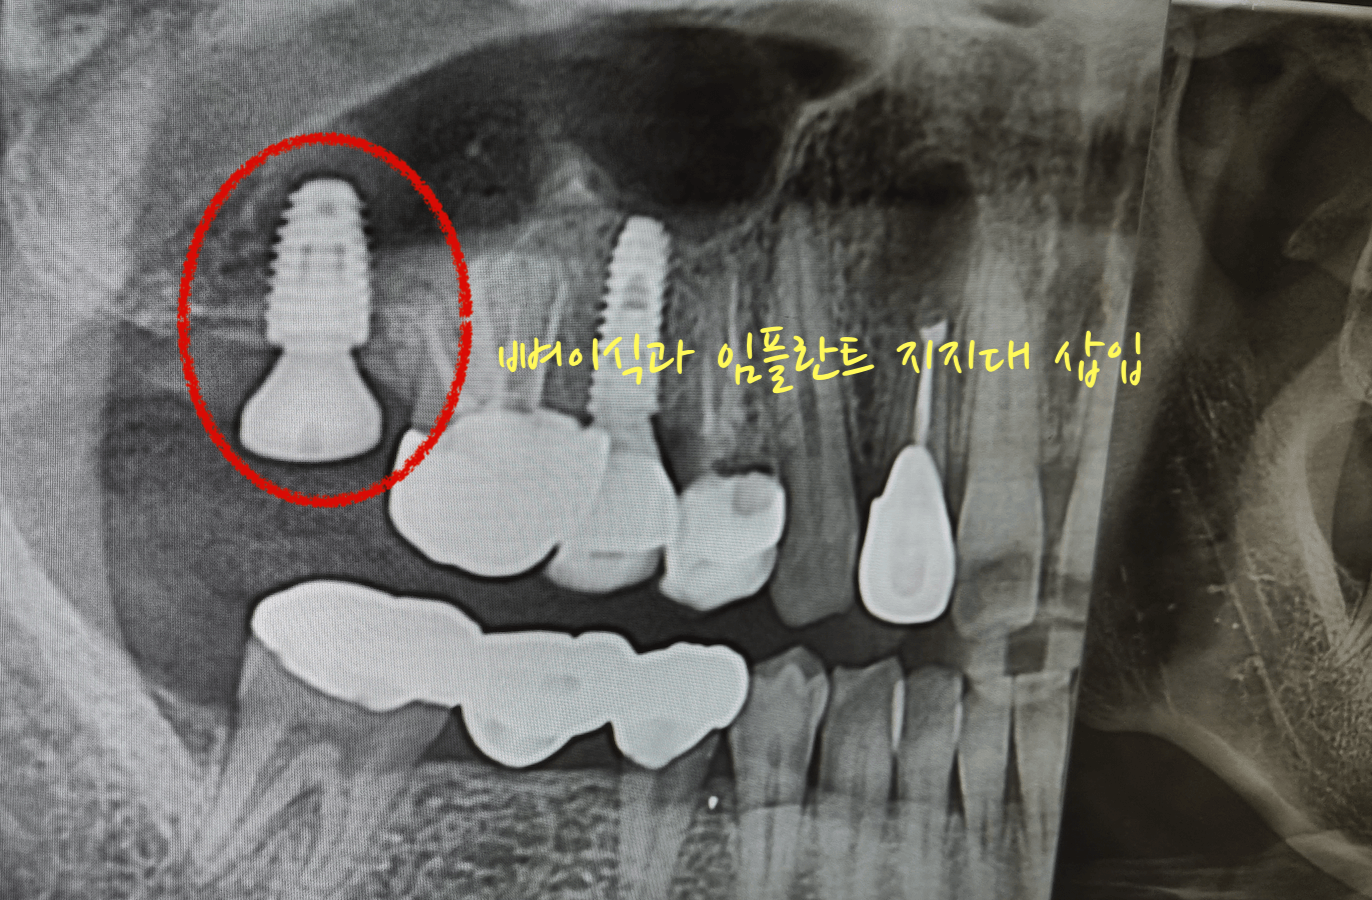

어금니 맨안쪽 치아를 염증 때문에 발치하고 3개월 뒤 어느 정도 뼈가 아물고, 오늘 해당 어금니 부분에 뼈이식과 임플란트 지지대를 삽입하고 왔습니다. 이것까지 하고 나서 치조골 이식한 것과 임플란트가 잘 아물면 그 이후 보철을 씌우면 됩니다.

이번 포스팅의 사진 또한 저의 치아 상태 사진 입니다. 그러니 불법으로 퍼가지 마세요, 부끄럽습니다. 대부분의 치아가 크라운을 씌우거나 임플란트를 해놓은거라 부끄럽네요. 대신 이모든것들이 직접 경험한 내용이기에 팩트는 확실히 전달 될것 같습니다. 아래 포스팅 또한 제가 모두 경험한 내용이니 참고하세요.